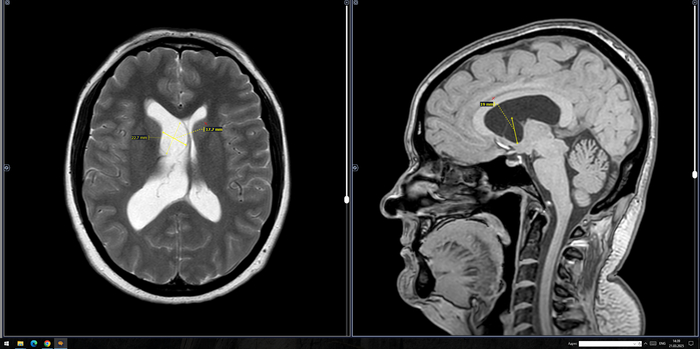

В расширенном турецком седле определяется солидное объемное образование неоднородно повышенного МР-сигнала на Т2 ВИ, размерами до 30 х 25 х 19 мм, неоднородно копит контраст. Образование распространяется в область кавернозных синусов по ходу С5 С6 сегментов внутренних сонных артерий, муфтообразно охватывая их до 70% окружности справа и до 50% окружности слева. Внутренние сонные артерии на уровне образования не сужены. Образование интимно прилежит к задним базальным отделам прямых извилин и зрительному перекресту, больше справа, без его оттеснения. Воронка гипофиза утолщена, отклонена вправо.На этом фоне нормальная структура гипофиза четко не определяется, вероятно, оттеснена вправо и кзади.

Заключение: МР- картина образования гипофиза, соответствует макроаденоме средних размеров с супра- и латероселлярным характером роста. Рек-но: конс. нейрохирурга.